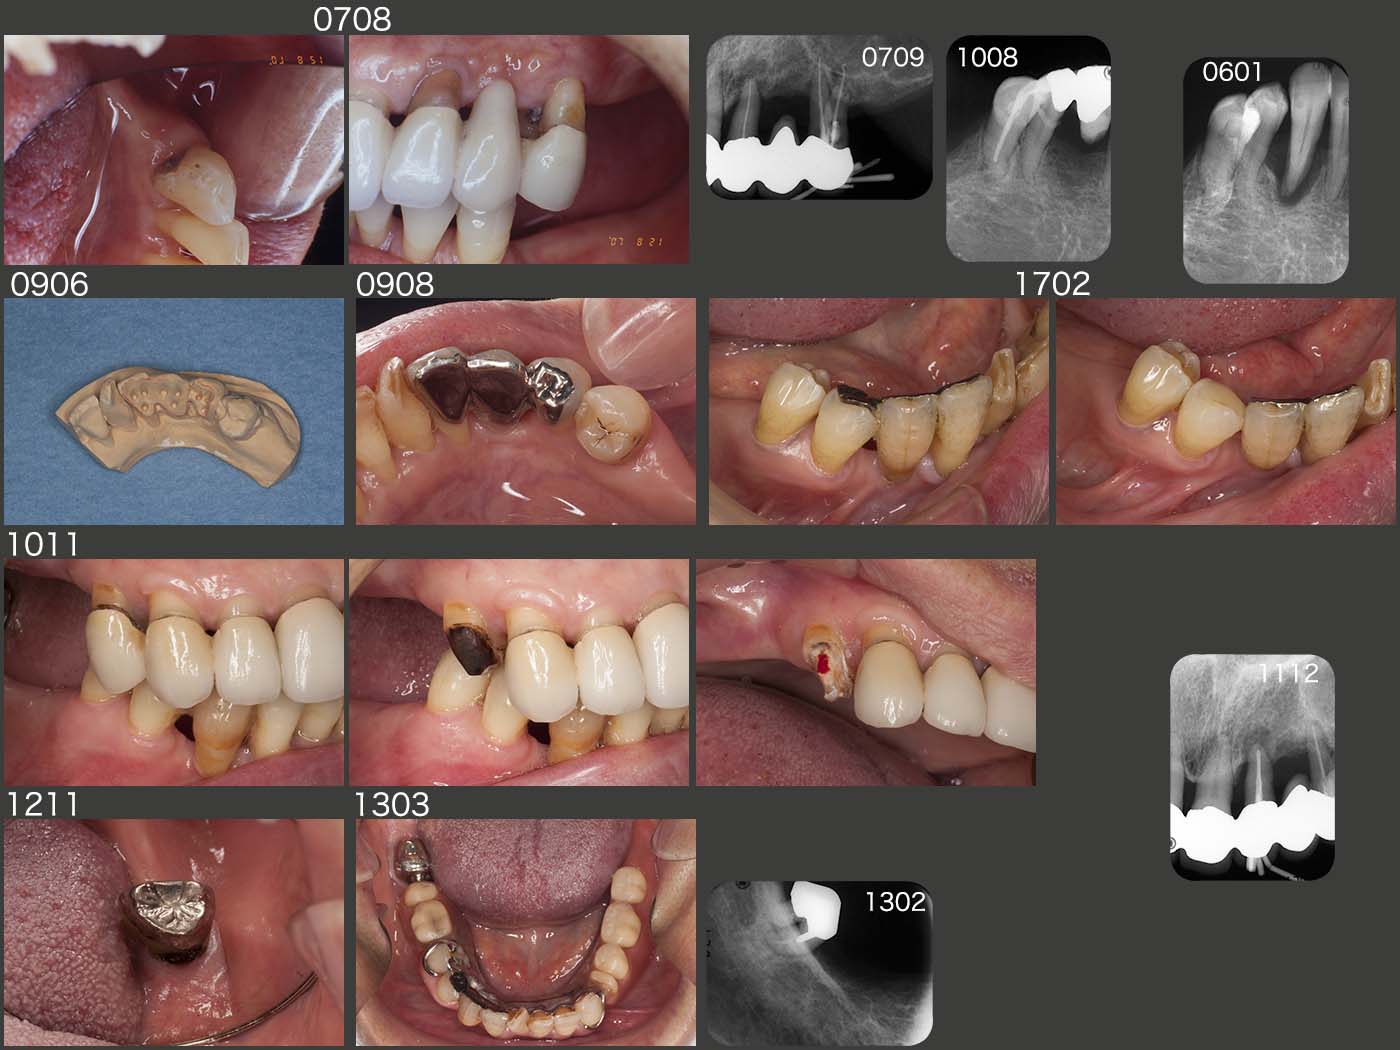

経過であるが,2007年8月のリコール時に,左下3,左上4および右下5(スライドに掲載なし)に根面カリエスが認められた.気管支炎でのど飴をよく舐めていたとのこと.これが原因で,9月に左上4を抜髄した.右下5は,う蝕が深かったからか10年8月にフィステルが生じ,歯髄が失活してしまった.

話は前後するが,06年1月,元々歯周病が進行していた右下3を抜去した.その後,歯冠部をスーパーボンドで隣在歯に固定していたが,時々外れるので,09年6月に,舌面板で連結固定した.しかし,17年2月,右下4の舌面板がセメントアウトしてしまった.右下3,4間で切断した状態で,20年11月まで何とか保っているが,延長ポンティック付きの右下2の動揺は著しく大きい.

また話は前後するが,10年11月,食事後義歯を外すときに痛みがあると訴えた右上4がセメントアウトしていた.右上3,4間で切断してみると,う蝕がかなり進行していた.今でこそAIPCを行うが,この時は露髄させてしまった.この歯は咬合支持歯であり,抜髄は何とか避けたく,カルビタールで暫く経過をみたあと,外れたメタルボンド冠の近心のコンタクトを回復し,再合着した.この歯は20年11月現在まで,特に問題が生じていない.抜髄しないで本当に良かった.

11年12月,左上2にフィステルが生じたため,感染根管治療を行った.

12年11月,右下8の遠心に根面カリエスが認められた.もう一度,クラウンを再製作しても,遠心の清掃は難しいと判断し,13年2月,金銀パラジウム合金で製作したコーヌス冠を装着した.こちらの方が,内冠が円筒形で清掃しやすいと思われる.